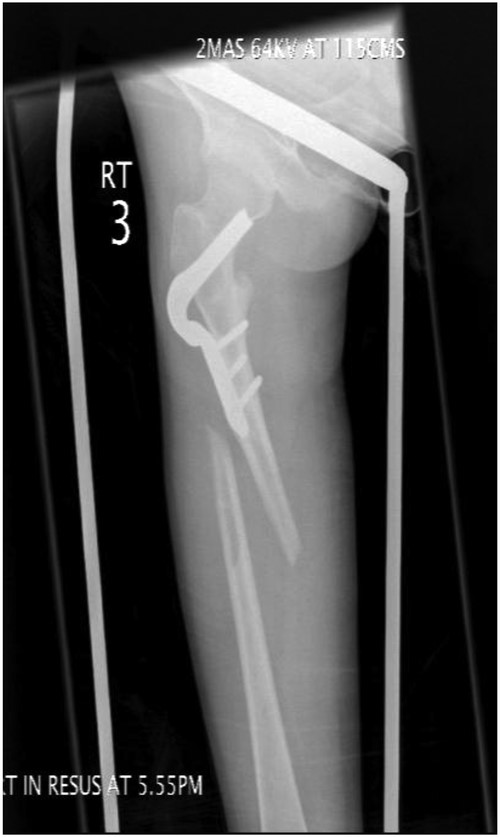

Under general anaesthesia, open reduction and internal fixation using a 10 hole philos plate was performed with the patient in a supine position on the traction table utilizing a lateral approach. Using C-arm image intensification, the height of the plate was judged, then applied to the bone and secured both proximally and distally to the fracture with proximal locking screws inserted where possible (Fig. 2a–c). Securing the cephalic segment of the philos plate to the proximal femur proved challenging due to the femoral neck defect left by the removal of the blade plate. Final reduction was judged to be near anatomical with the wound thoroughly irrigated with saline before closure. Post-operative treatment included IV antibiotics with mobility instructions unnecessary due to the patient's non-ambulatory status. The patient was discharged after 5 days with a follow-up period over 11 months. There were no post-operative complications during this time and radiographs showed an anatomically healed fracture (Fig. 3).

AP-XR demonstrating radiographic union at 11 months with 10 hole PHILOS insitu.